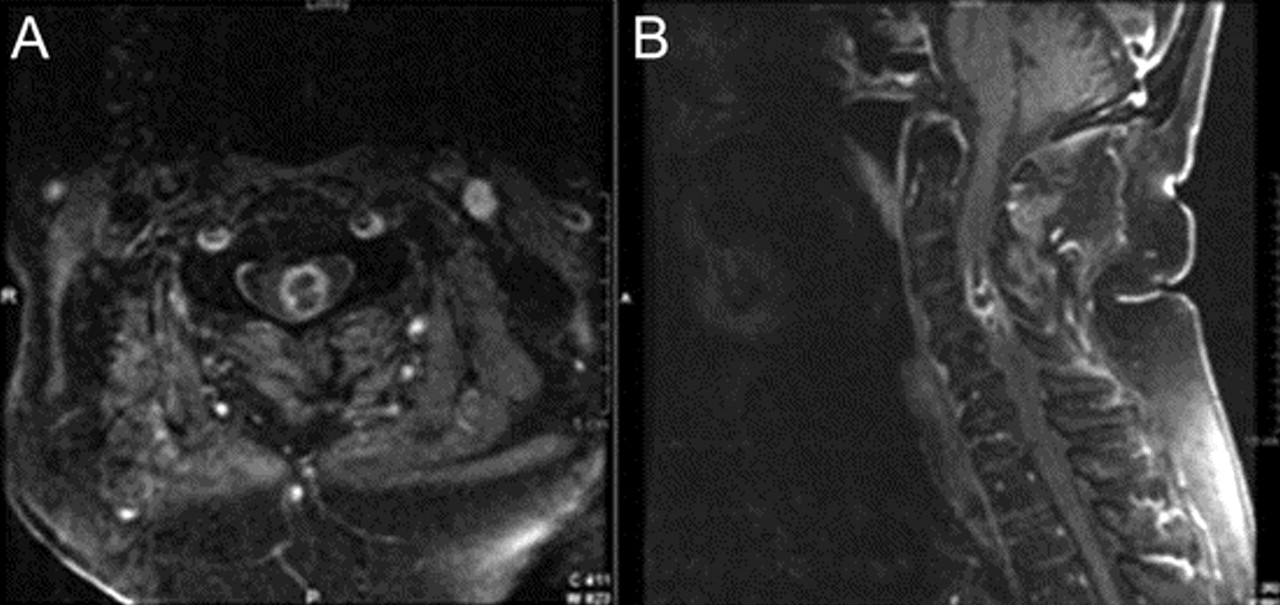

一个79岁的老人对慢性溃疡性结肠炎强的松治疗发展严重midcervical疼痛和进步的弱点在几天左胳膊和腿。这是与左前臂感觉异常和泌尿犹豫和尿失禁。他没有颅或延髓的症状。一般检查,他无热的但是有midcervical脊柱疼痛。神经系统检查发现正常的精神状态和颅神经;力量是2/5在左边,右边和4/5;对疼痛的感知水平和温度对C4的权利,减少了本体感受的左脚和手;有一个左巴宾斯基的信号和一个哑巴右足底的回应。白细胞计数为18.2×109/ L。血培养结果为阴性。胸部CT显示多个肺结节。颈椎核磁共振(图1)左边显示髓内ring-enhancing质量与水肿从C2 C7相关疼痛。脊髓切片显示开放诺卡氏菌属farcinica脓肿(图2)。腰椎穿刺和支气管镜检查没有进行。病人甲氧苄氨嘧啶IV和地塞米松治疗。10天后,下肢力量改善双边。左手臂力量和感觉赤字保持不变。他8周后死于心脏骤停。不需要进行尸检。

图2分支,丝状,串珠细菌内坏死碎片

微生物被GMS(银)和彩色菲特(快速修改酸)污渍;他们没有污点Ziehl-Neelsen革兰染色(传统酸快速)或组织。形态和染色特征最符合诺卡氏菌属的物种。菲特染色在100×(油)。